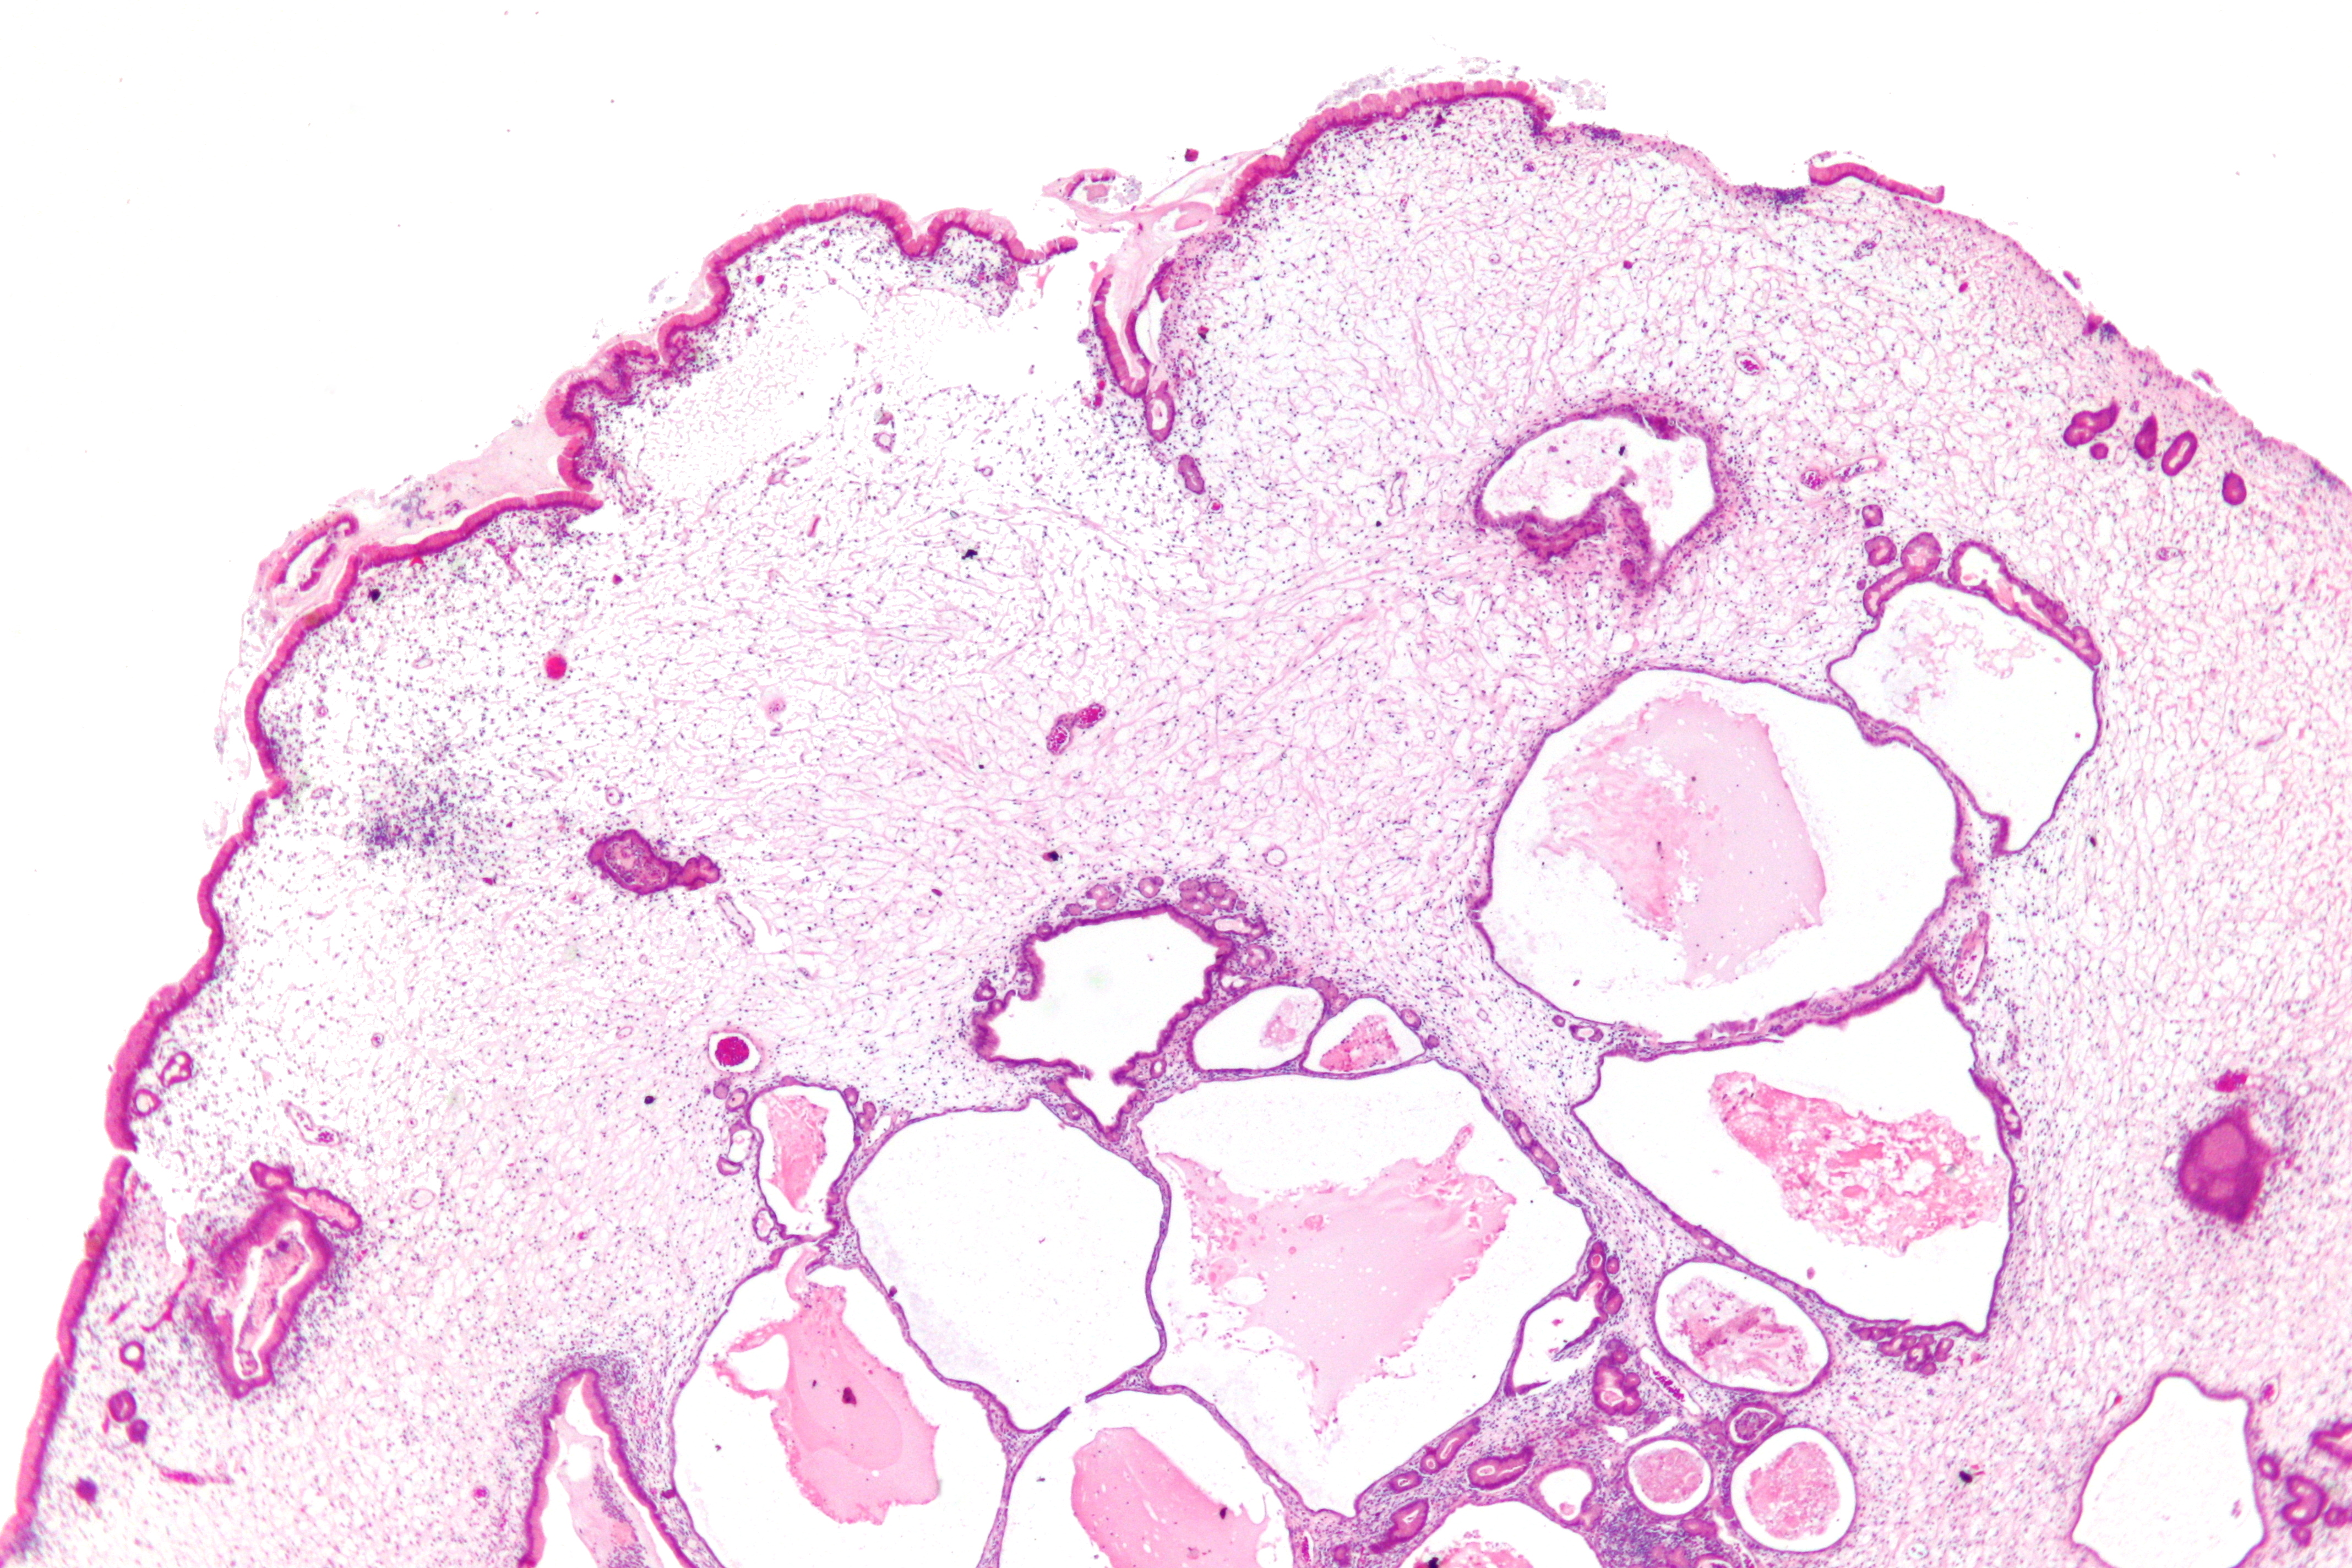

| 샘 용종 | 위의 바닥 | 주세포, 벽세포 및 점액성 와상 세포로 덮인 낭성 확장된 샘[5] | 산발적인 경우 매우 낮거나 없음[6] | ![]() | 샘 용종증 |

| 샘 용종 | 위의 바닥 | 주세포, 벽세포 및 점액성 와상 세포로 덮인 낭성 확장된 샘[5] | 산발적인 경우 매우 낮거나 없음[6] | 샘 용종증 | |